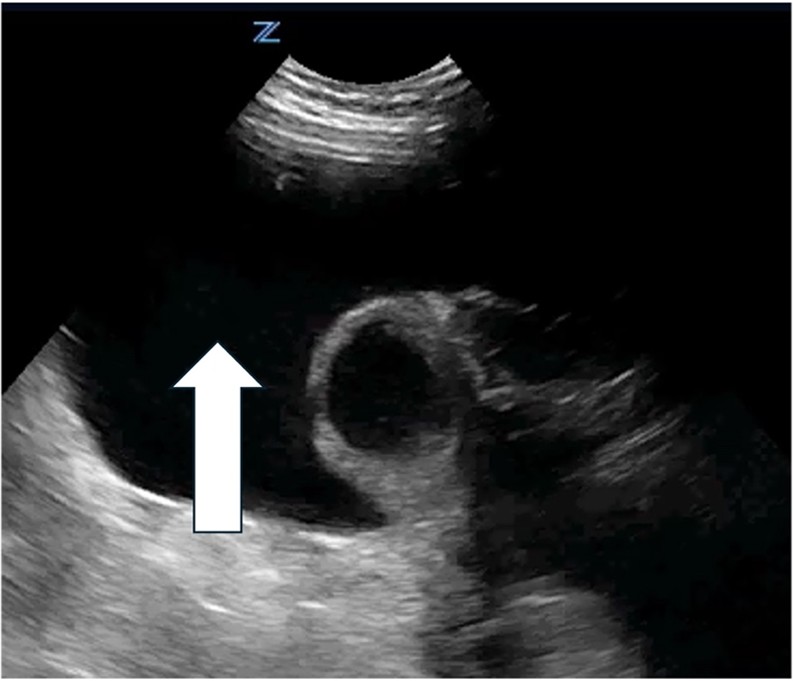

![]() |

Arrow indicates a septated peritoneal fluid collection |